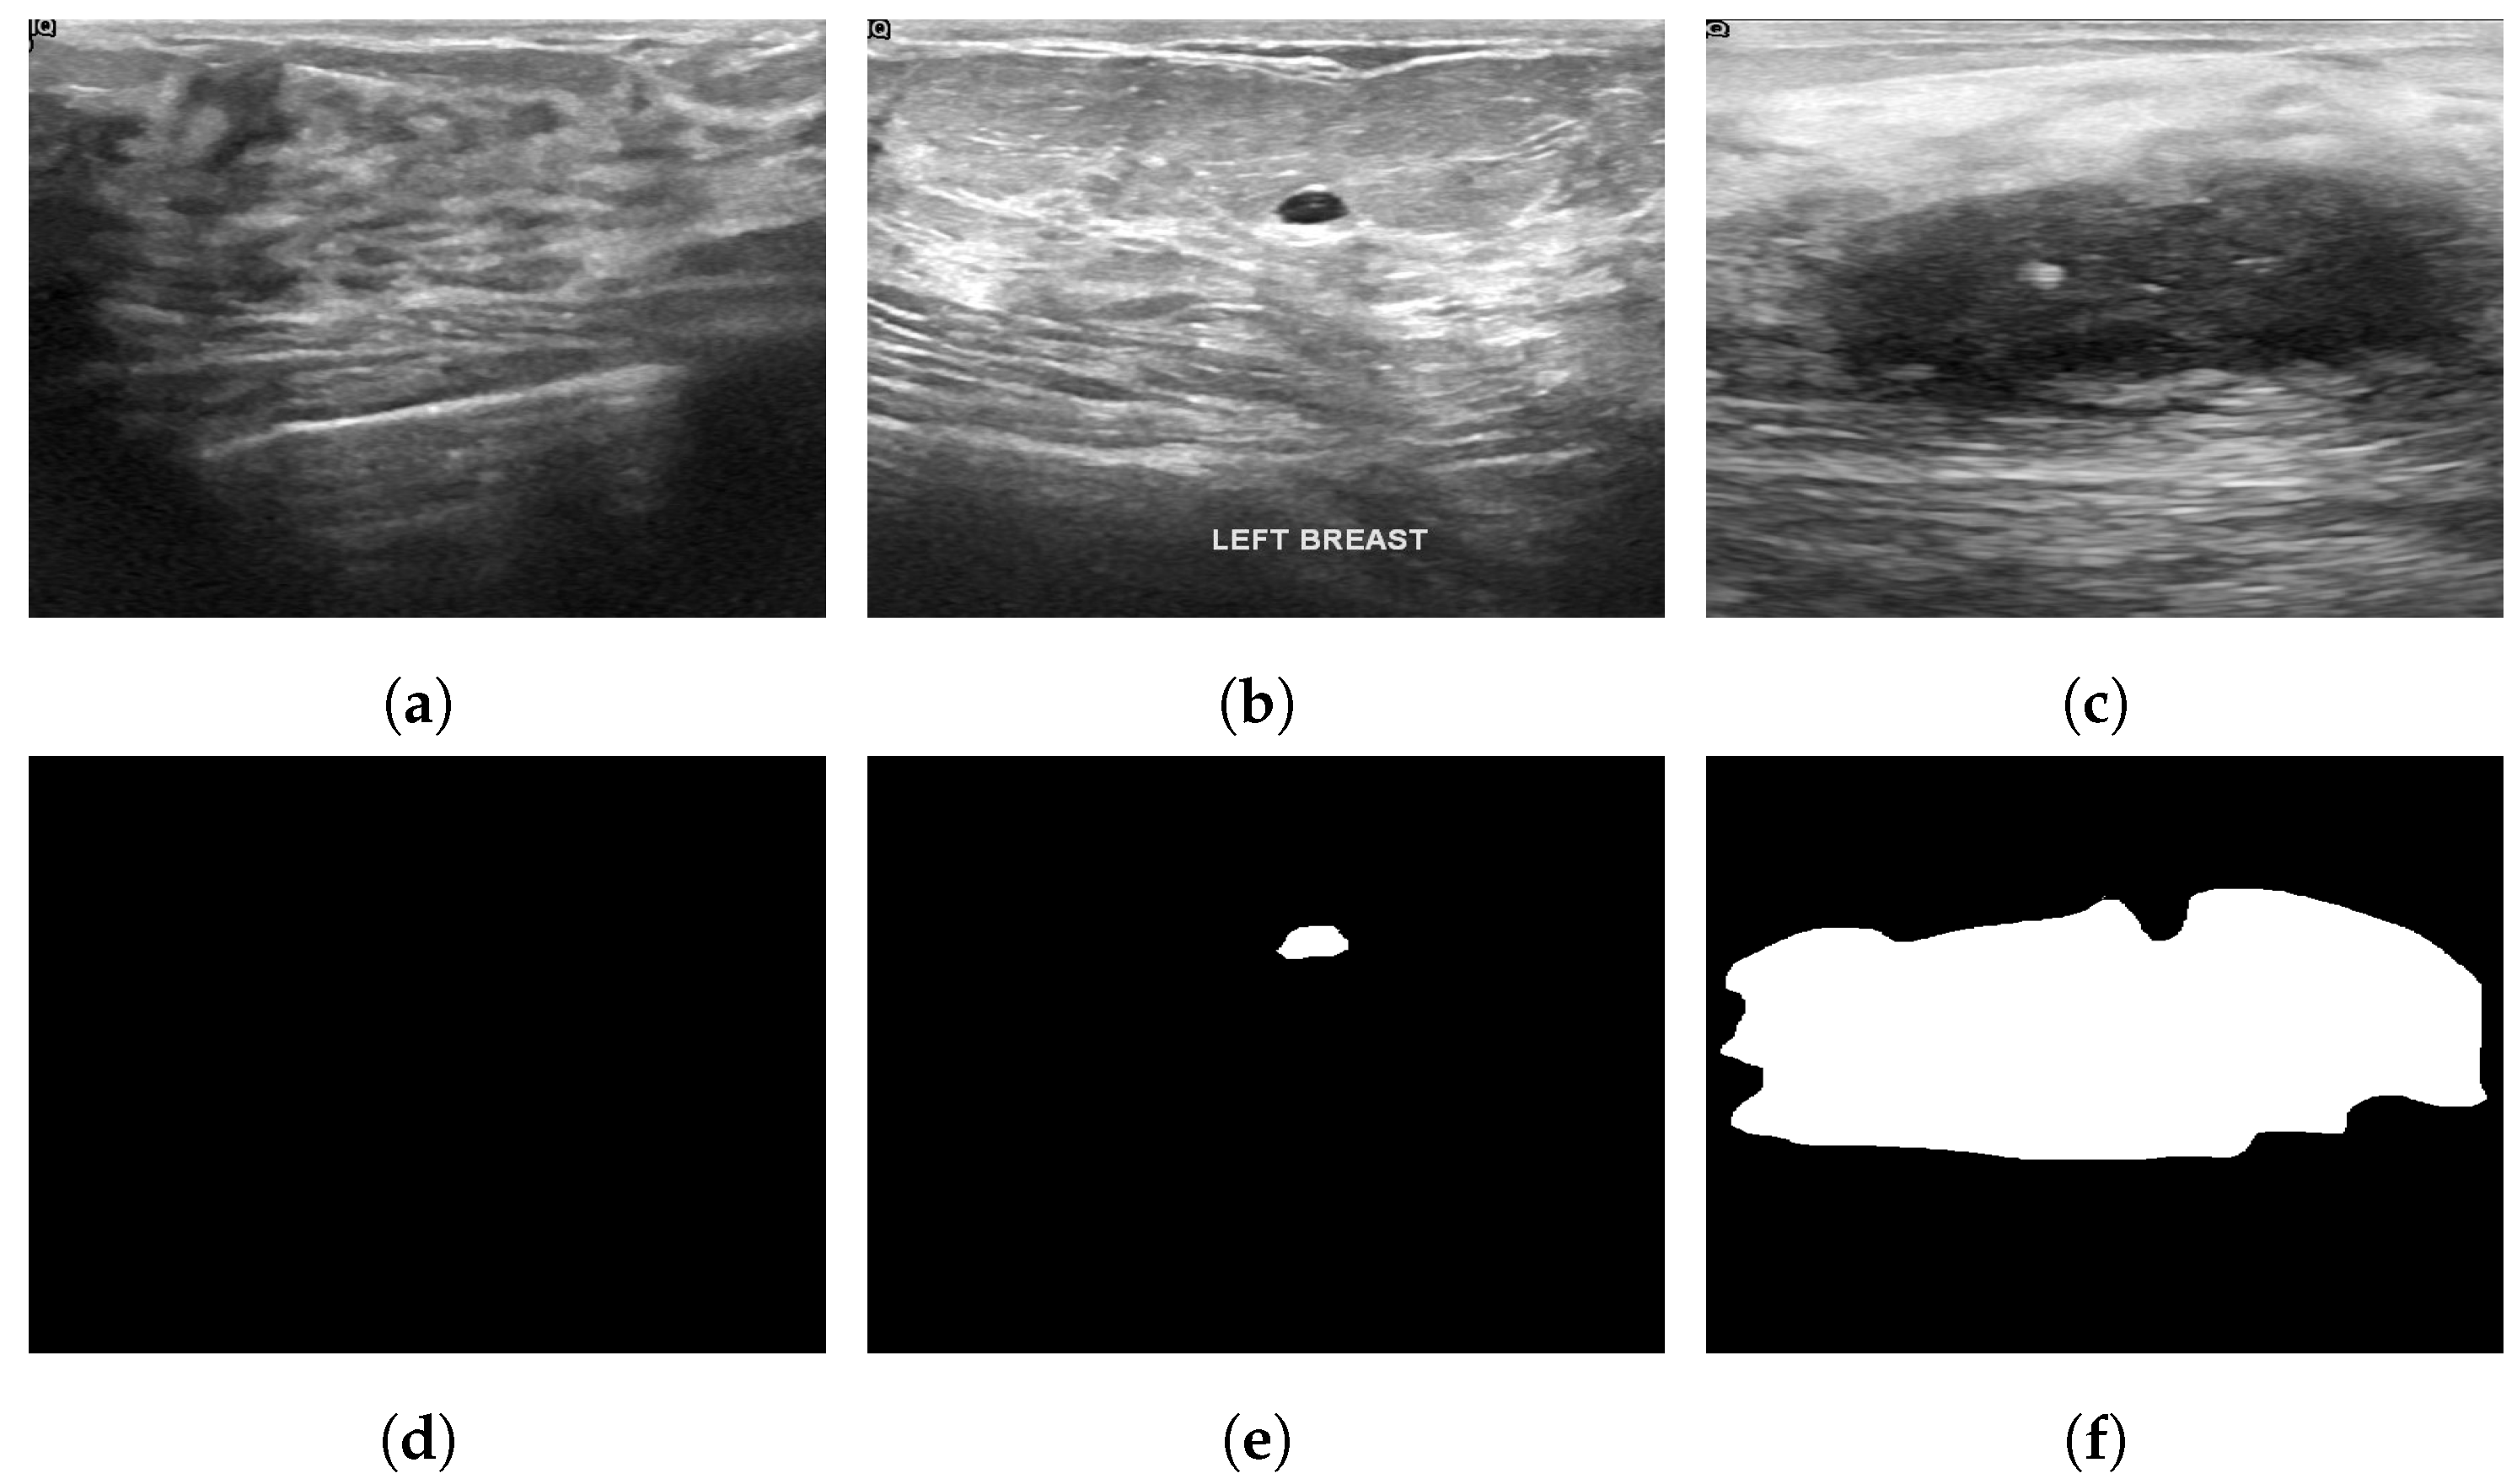

4.3. Ultrasonography

- Almajalid, R.; Shan, J.; Du, Y.; Zhang, M. Development of a Deep-Learning-Based Method for Breast Ultrasound Image Segmentation. In Proceedings of the 2018 17th IEEE International Conference on Machine Learning and Applications (ICMLA), Orlando, FL, USA, 17–20 December 2018; pp. 1103–1108. [Google Scholar]

- Yap, M.H.; Pons, G.; Martí, J.; Ganau, S.; Sentis, M.; Zwiggelaar, R.; Davison, A.K.; Marti, R. Automated breast ultrasound lesions detection using convolutional neural networks. IEEE J. Biomed. Health Inform. 2017, 22, 1218–1226. [Google Scholar] [CrossRef]

- Ilesanmi, A.E.; Chaumrattanakul, U.; Makhanov, S.S. A method for segmentation of tumors in breast ultrasound images using the variant enhanced deep learning. Biocybern. Biomed. Eng. 2021, 41, 802–818. [Google Scholar] [CrossRef]

- Huang, K.; Zhang, Y.; Cheng, H.; Xing, P.; Zhang, B. Semantic segmentation of breast ultrasound image with fuzzy deep learning network and breast anatomy constraints. Neurocomputing 2021, 450, 319–335. [Google Scholar] [CrossRef]